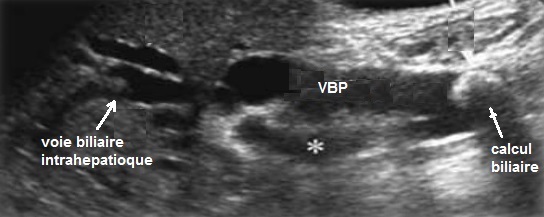

Image echographique : Image

echographique a susgestion de syndrome Mirizzi est image d'une

calcule en coince a infundibulum de la vesicule biliaire ou

intraluminal du canal hepatique commun . Une dilatation de

voie biliaire principale et et des voies biliaires

intrahepatiques en amont est souvant se presente .Et image d' une inflammation chronique de

vesicule biliaire etre en voyait

Dilatation des voies biliaires

intrahepatique et du canal hepatique commun par obtruction

mecanique calculaire : Image echographique

percutane du foie |

Image echographique

d'une calcul du collet vesiculaire compressee sur

le canal hepatique commune . Les voies biliaires en

amont sont dilatees . Vesicule biliaire est en

inflamee a paroi tres epais ( cholecystite chronique

) :: Syndrome de Mirizzi |